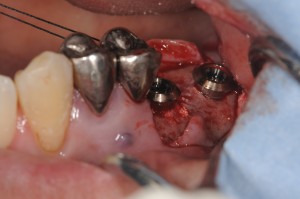

この症例は、午後のオペで右上の6,7番部位にストローマンインプラントの大臼歯用1回法のワイドネックΦ4.8mmを2本使いました。

6と7番の間にかなり高い中隔がありましたので、ラテラルアプローチではなく、オステオトームテクニックを用いました。

最終のオステオトームΦ4.0mmで骨補てん材を入れて、ボディー径Φ4.2mmのワイドネックをセルフタップで埋入しました。

これにより、手指感覚では、しっかりとした固定が得られましたので、1回法でオペを終了しています。

オステオトームテクニックで補てん材を填入しながら、粘膜を挙上していきます。

7番部位の骨が薄いところは、ドリリングで穿孔しないようにピエゾサージェリーを使用して、ソケットホールを形成します。

使用したストローマンワイドネック8mmのSLActiveです。

埋入が終了したところですが、しっかり固定ができています。